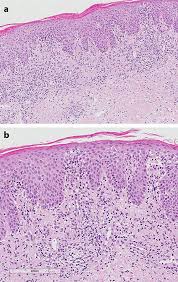

Drug reaction with eosinophilia and systemic symptoms dress also termed drug induced hypersensitivity syndrome dihs is a rare reaction to certain medications.

Dress syndrome. The first signs of dress are usually a fever followed by a rash. This is an adverse reaction of drugs which potentially causes life threatening hypersensitivity reaction and involving systemic circulation and major organs including lungs liver and kidney. The syndrome is classified as a severe cutaneous adverse reaction scar.

Though fever rash and eosinophilia dress syndrome. Dress syndrome has been caused by many drug classes in the past most notably the anti seizure medications and antibiotics. The associated mortality rate for dress syndrome is from 5 10.

Most patients with dress will have an abnormal level of blood cells found in their blood tests which are called eosinophils. Dress is also frequently associated with a viral infection or reactivation called hhv 6. Dress is an abbreviation of drug reaction with eosinophilia and systemic symptoms.

Drug reaction with eosinophilia and systemic symptoms dress syndrome is a serious and potentially fatal adverse effect to therapeutic medications.